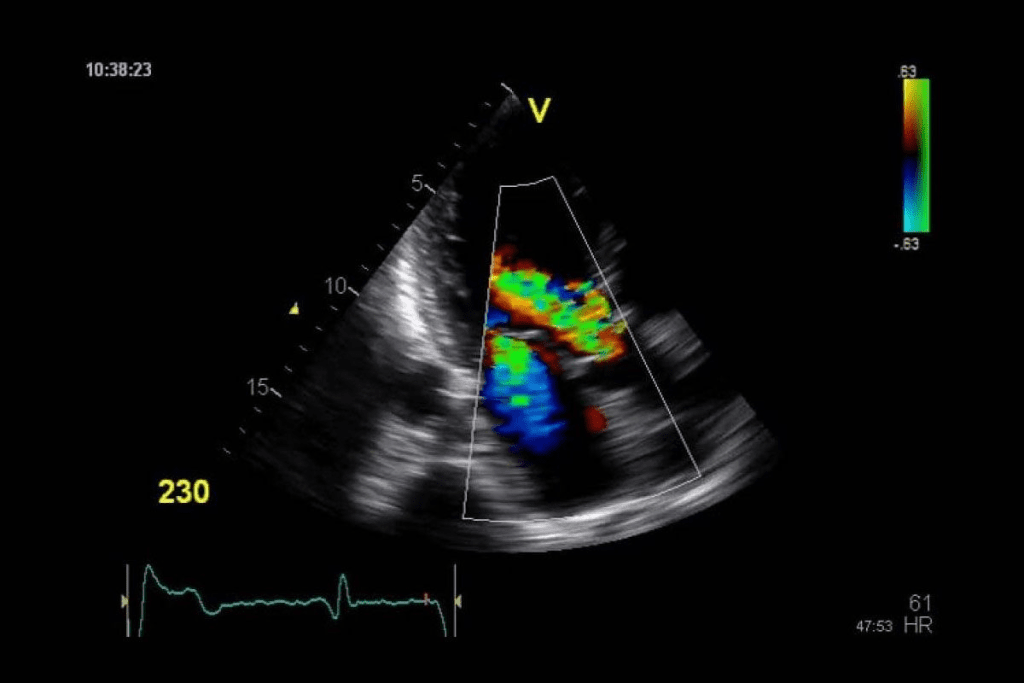

Power Doppler and Other Color Variations

Power Doppler is great for finding slow blood flow in small vessels or tumors. It doesn’t show flow direction like regular color Doppler does. It just shows there’s flow.

Other variations, like directional power Doppler, add flow direction to power Doppler’s sensitivity. These advanced methods help doctors understand blood vessel health better.

Blood flow patterns seen with Color Doppler ultrasound are vital in cancer diagnosis. Malignant tumors show increased vascularity and abnormal blood flow patterns. This shows their aggressive nature.

Using advanced ultrasound like Power Doppler helps see blood flow better. This helps tell if a tumor is benign or malignant.

Tumor Vascularity and Blood Flow Patterns

Tumors grow and spread by getting a blood supply. Tumor vascularity is when new blood vessels form in a tumor. Doppler ultrasound can spot these vessels and check their blood flow.

Malignant tumors have special blood flow patterns. They have more blood vessels and irregular shapes. Doctors can learn about the tumor by looking at these patterns.